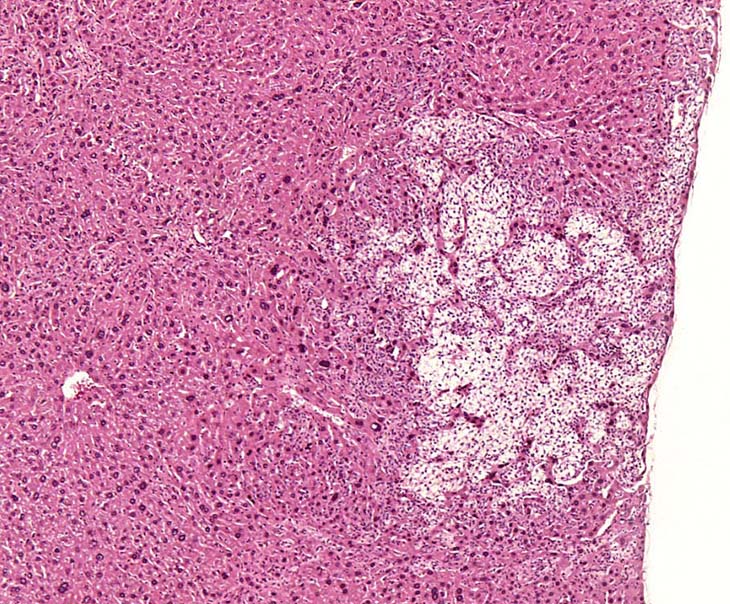

A relative discrete Ito cell tumor is present within this hepatic lobe; a higher magnification shows proliferation of stellate cells within the hepatic sinusoidal spaces.